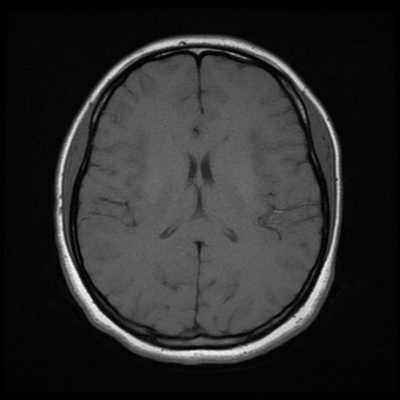

Классический пример МРТ снимков головного мозга показан на рисунках ниже. Магнитно-резонансная томография выполняется в поперечной (или аксиальной - рисунок снизу) и продольной (или сагиттальной — рисунок сверху) плоскостях.

Исследование выполняется в нескольких режимах. Основные из них Т1 и Т2. Изображения, полученные в данных режимах, часто также называют Т1-взвешенными или Т2-взвешенными снимками. Изображения, показанные выше, сделаны в Т1-режиме.

Главное отличие этих режимов - в том, как на снимках отображается жидкость и воздух. В Т1 режиме ткани, содержащие большое количество воды, имеют более темную окраску, в то время как в Т2 режиме они яркие, светлые. Это легко понять, посмотрев на снимки выше - глазные яблоки визуализируются в виде светлых парных округлых образований с одной стороны яркие и светлые, с другой - темные. Следовательно, снимок справа сделан в Т1 режиме, снимок слева - в Т2. Также существует разница в том, как в этих режимах отображается серое вещество головного мозга. В Т2 режиме оно светлее, чем белое вещество.